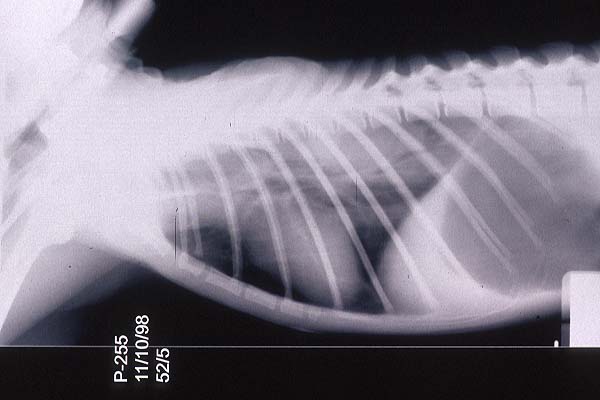

- Case 23-1. Chest radiograph. Diffusely lung fields

are infltrated by flocculent fluid densities.